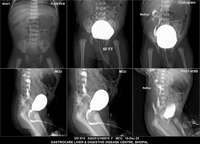

Section: URETHROGRAM Total: 95 images

BaM Enteroclysis Loopogram BaE Fistulogram Urethrogram HSG